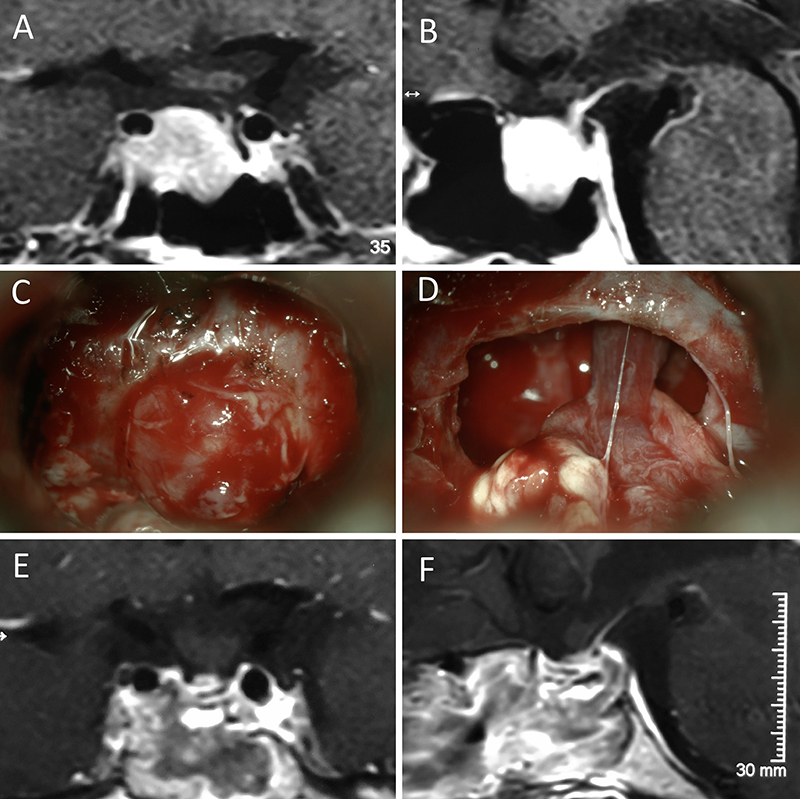

Figura 6: Apoplejía hipofisaria hemorrágica en un hombre de 55 años. El paciente presentó cefalea, déficit visual y parálisis completa del III par. Evolucionó favorablemente tras la cirugía, revirtiendo el cuadro. A-B: RM preoperatoria; C-D: intraoperatorio; E-F: RM postoperatoria.

Figura 7: Acromegalia en mujer de 39 años. Con remisión bioquímica tras la cirugía. A-B: RM preoperatoria; C-D: intraoperatorio; E-F: RM postoperatoria.

Figura 8: Acromegalia en mujer de 50 años. Con remisión bioquímica tras la cirugía. A-B: RM preoperatoria; C-D: intraoperatorio; E-F: RM postoperatoria.